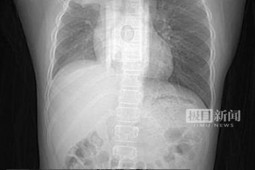

Theo đó, cậu bé này sau khi bị cảm lạnh thường kêu đau tai, gia đình đưa đi khám thì kết quả khiến mọi người sửng sốt. Tai của cậu bé bị bịt kín bởi một cục ráy rai khổng lồ, cứng như xi măng.

Bác sĩ cho biết, tai của cậu bé bị đau là đo ráy tai đã bị kín ống tai lâu ngày, cộng với cảm lạnh nên gây ra tình trạng viêm tai giữa. Nếu không kịp điều trị có thể khiến cậu bé bị điếc vĩnh viễn, viêm màng não, thậm chí có thể nguy hiểm đến tính mạng.

Để chữa trị bệnh viêm tai giữa cho cậu bé, trước tiên bác sĩ vệ sinh sạch sẽ tai, nhưng vì ráy tai quá nhiều và cứng nên ca mổ buộc phải gây mê toàn thân.